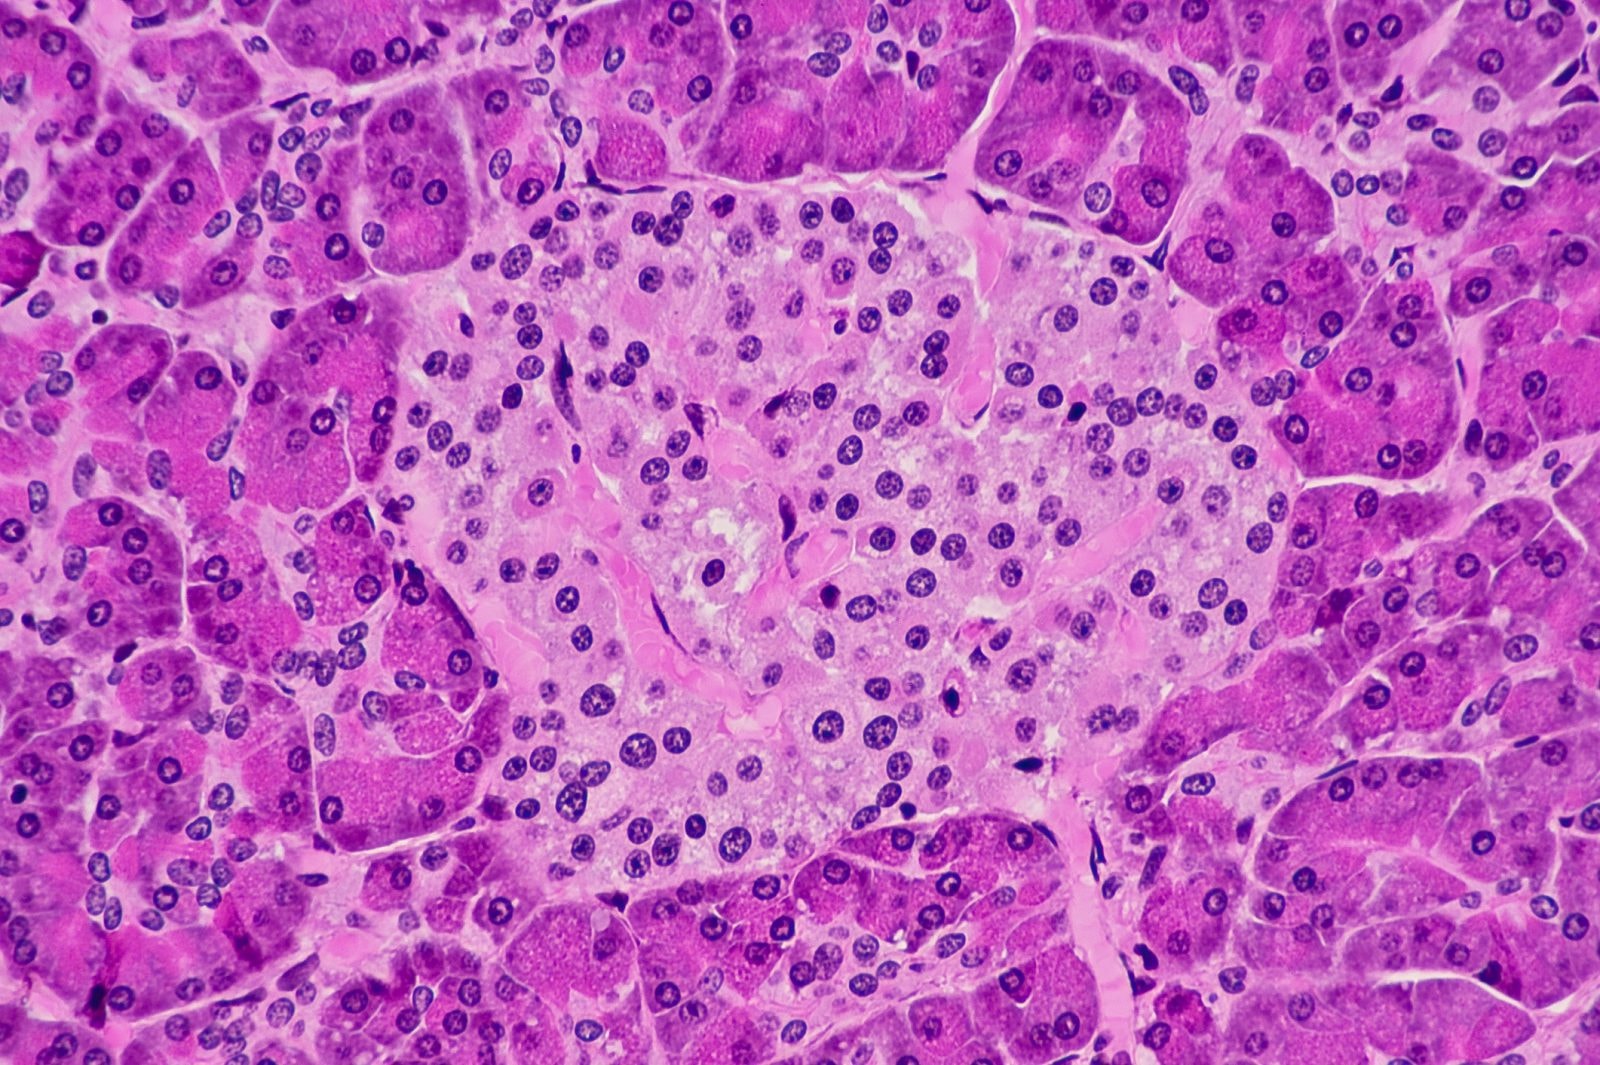

Na https://www.focus.pl/artykul/typ-2-cukrzycy-nie-istnieje-mozliwe-ze-przez-lata-bylismy-w-bledzie-180302015730 choruje ponad 420 mln osób na całym świecie. W cukrzycy typu 1, która dotyczy ok. 10 proc. pacjentów, niezbędne jest https://www.focus.pl/artykul/pompa-insulinowa – hormonu obniżającego poziom glukozy we krwi. Dzieje się tak, ponieważ w trzustce zniszczone zostają komórki beta wysepek Langerhansa, produkujące insulinę. Ta odmiana cukrzycy atakuje przede wszystkim dzieci i młodych ludzi.

Jednak i w tym przypadku problemem jest mała dostępność komórek, pobieranych od dawców. Podejmowano próby wykorzystania wysepek trzustkowych pobranych np. od świń. Jednak tak obce komórki były atakowane przez układ odpornościowy pacjenta i przeszczep się nie przyjmował.

Amerykańska firma Viacyte (wcześniej zwana Novocell) poszła inną drogą. Wykorzystuje pobrane z ludzkich zarodków https://www.focus.pl/artykul/zastrzyk-nadziei-falszywe-terapie-komorkami-macierzystymi. To uniwersalne komórki, z których mogą powstać inne, bardziej wyspecjalizowane rodzaje komórek. Uczeni potrafią już sterować rozwojem komórek macierzystych tak, aby powstały z nich komórki produkujące insulinę.

W pierwszej pracy badacze wykazali, że przeszczepione komórki macierzyste faktycznie produkują insulinę w organizmach pacjentów chorych na cukrzycę typu 1. Implant potrzebował na to ponad pół roku, ale gdy zawarte w nim komórki dojrzały, zachowywały się zgodnie z oczekiwaniami. Przez rok obserwacji pozwoliły pacjentom ograniczyć o 20 proc. dawki przyjmowanej insuliny. – To pierwsze tego typu badania na świecie – podkreśla szef zespołu badawczego prof. Timothy Kieffer.